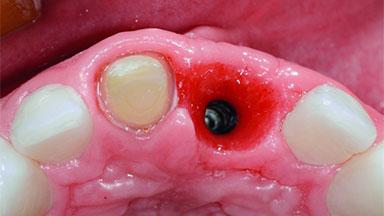

A 15-year-old male patient was referred to us by his pediatric dentist in June 2004 for evaluation of treatment options for his failing tooth 21. The patient had recently seen an endodontist for internal bleaching and been advised that there had been significant resorption and ankylosis. The patient’s mother was concerned because the tooth appeared shorter than the adjacent one. His past dental history was significant for trauma (September 2001), where the tooth had been avulsed and reimplanted. Teeth 11 and 21 had been endodontically treated.